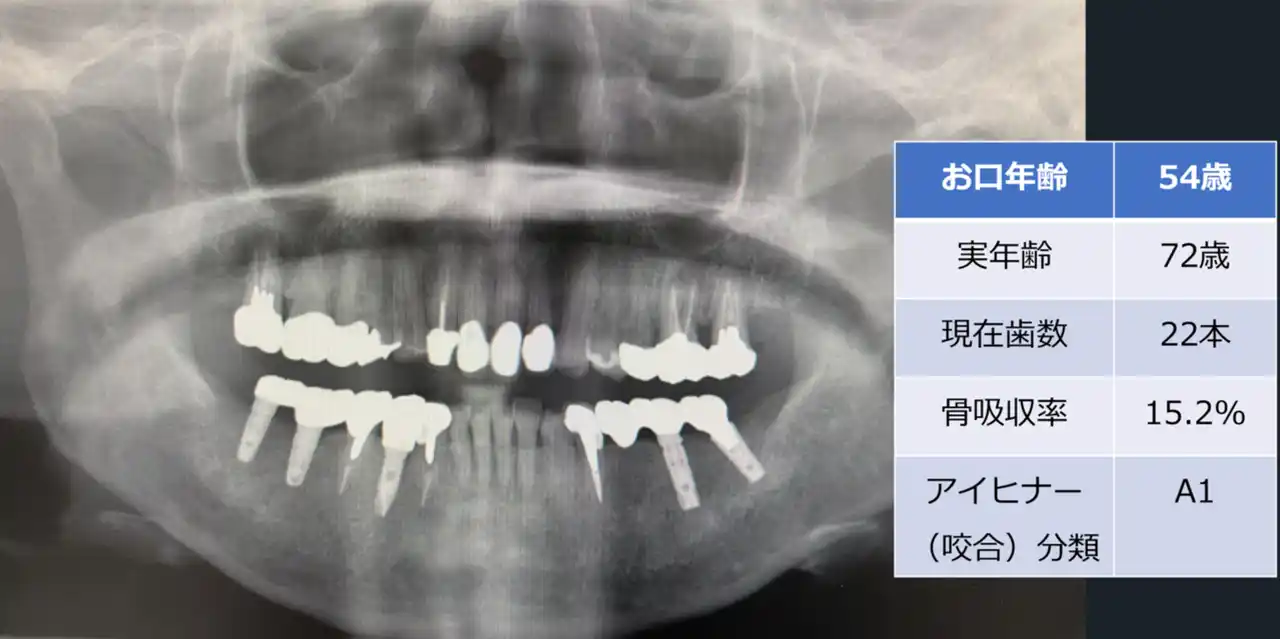

【医療法人社団 葵会】 歯科エックス線画像を用いた「お口年齢AI」の開発について by PR TIMES

予防歯科・お口の健康から、人生100年時代の健康寿命延伸へ   医療法人社団 葵会(統括本部:千葉県柏市、理事長:新…